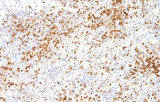

- Assegnazione del lignaggio & principali diagnosi differenziali: Fenotipizzazione cellule B vs cellule T (es. CD20 vs CD3), supportata da fattori di trascrizione nucleari delle cellule B come PAX5 quando i marcatori pan-B sono deboli/assenti.

- Linfoma follicolare: tipici pattern di co-espressione (es. CD10 con BCL2 aberrante).